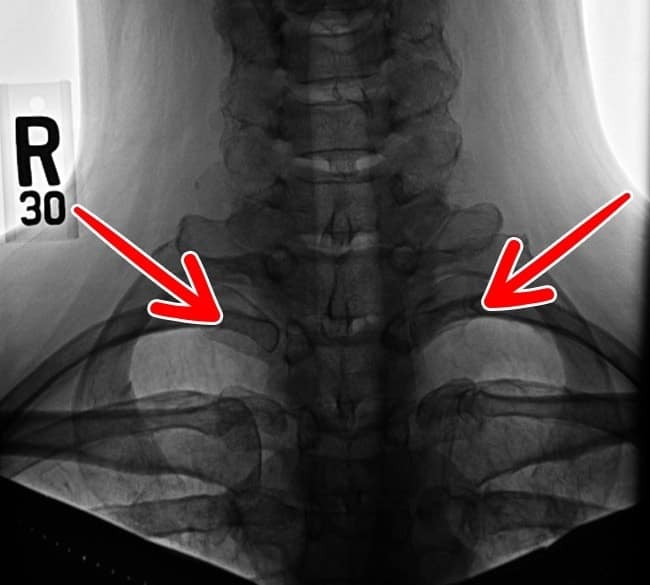

5. Costela cervical

Um grupo dessas costelas existe em menos de 1% dos seres humanos. Há quem tenha do lado direito ou do esquerdo e ainda existem pessoas que têm nos dois lados.

Normalmente, as costelas originam transtornos associados ao sistema nervoso ou arterial.